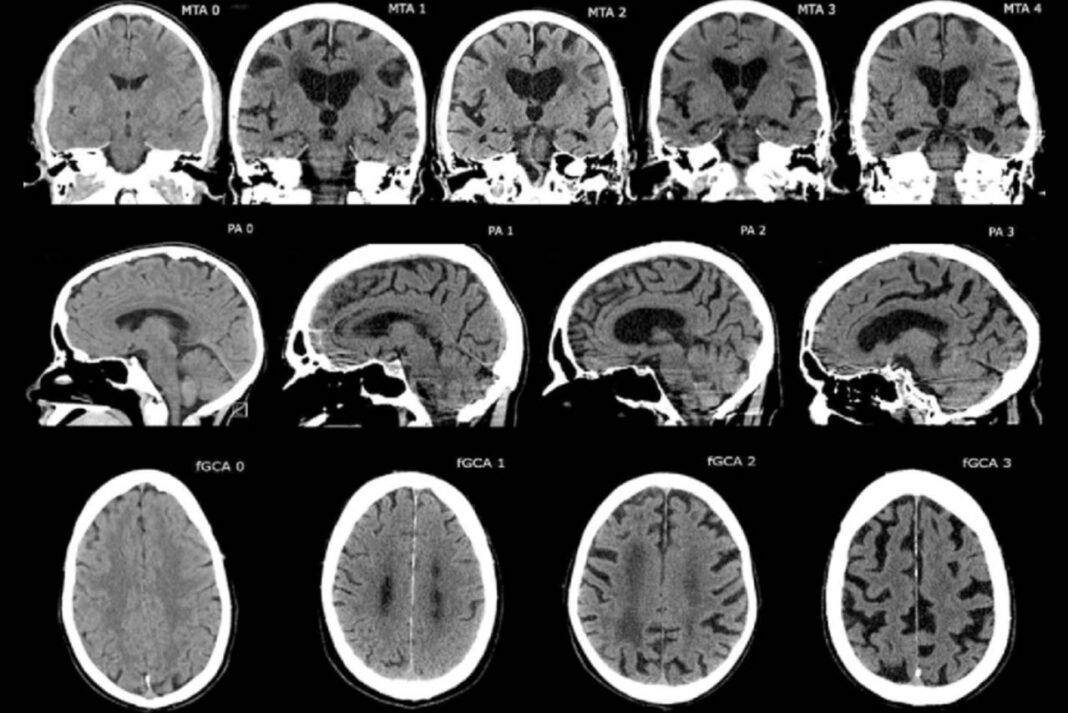

Brain imaging techniques (MRI, CT)